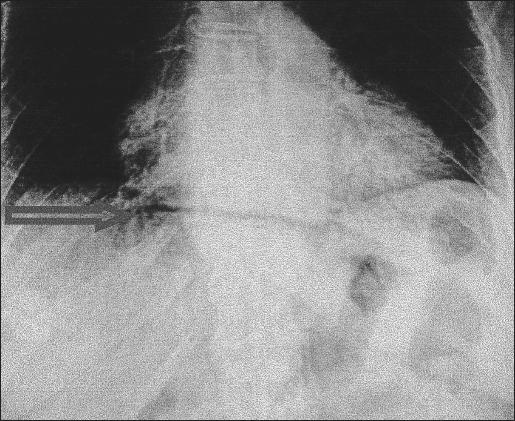

A 75-year-old woman affected by cirrhosis of the liver (Child class C) and chronic gastric ulcer presented with acute abdominal pain. The diagnosis of perforation was made with plain films of the abdomen and computed tomography. Diagnostic laparoscopy showed intense peritonitis due to a perforated ulcer of the anterior gastric wall, 2 cm proximal to the pylorus. Suture closure and placement of an omental patch were performed laparoscopically.

一名75岁患有肝硬化(Child C级)和慢性胃溃疡的女性出现急性腹痛。通过腹部平片和计算机断层扫描做出穿孔诊断。诊断性腹腔镜检查显示,幽门近端2厘米处的胃前壁溃疡穿孔导致严重腹膜炎。通过腹腔镜进行缝合关闭和网膜补片放置。